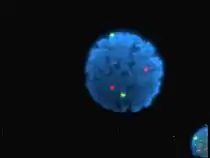

Noyau de lymphocyte humain coloré au DAPI avec les chromosome 13 (vert) et 21 (rouge) par des sondes hybridées aux centromères (hybridation in situ en fluorescence).